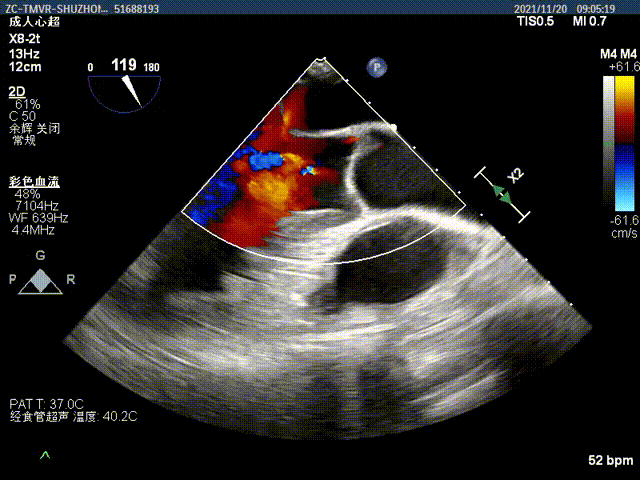

术后无瓣周漏

手术采用左侧第六肋间微创切口心尖入路,在超声引导下,清晰识别MitraFix®输送系统准确跨瓣,并将人工瓣膜准确释放于二尖瓣瓣环,术中超声发现局部介入瓣环位置偏低,及时换为手动输送器固定模式,精细调整介入瓣的左心房伞盘位置,最终瓣膜释放后支架贴合牢固,无瓣周漏及瓣内返流,二尖瓣前向血流通畅,左心室流出道通畅,流出道血流速度为2.4 m/s. 顺利撤出输送系统,关闭心尖切口无出血,手术顺利结束。患者射血分数仅30%左右,心脏功能差,麻醉后血压一度需要多巴胺和肾上腺素等药物维持,瓣膜置换后即刻血压升高,出手术室时候所有血管活性药物全部减停了。第二天顺利拔除气管插管。